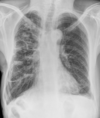

A: edema alveolar B: líneas B de Kerley C: cardiomegalia D: dilatación de vasos en lóbulos superiores E: derrame pleural

Insuficiencia cardiaca